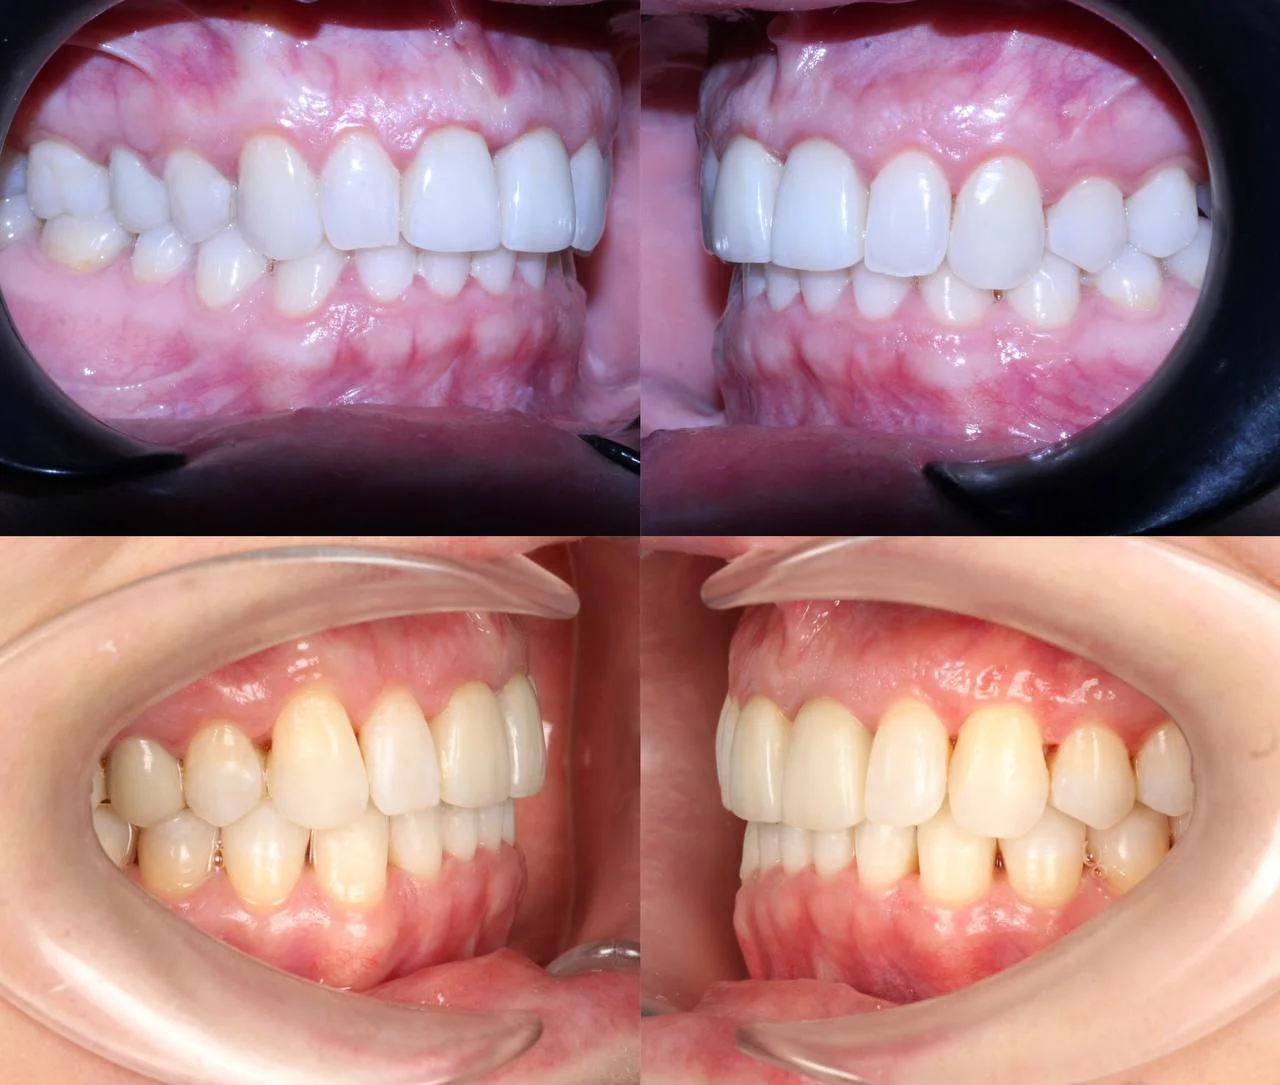

Верхняя челюсть выступала вперёд относительно нижней с обеих сторон (II класс по Энглю). Обе челюсти сужены, зубы стояли скученно. Нарушена кривая смыкания — жевательные зубы были на разной высоте. На двух передних зубах верхней челюсти ранее установлены металлокерамические коронки.

Прозрачные элайнеры Click на обе челюсти. Расширить зубные дуги, убрать скученность, исправить прикус и выровнять линию смыкания. Лечение с учётом имеющихся коронок. Основной набор — 31 капа. Срок — около 1,5 лет.

Результат

Зубы выровнены, скученность устранена, прикус исправлен, линия смыкания нормализована. Ретейнер установлен на нижнюю челюсть. На верхней ретейнер не ставили — на передних зубах коронки, вместо этого изготовлены ретенционные капы на обе челюсти. Пациентка направлена к ортопеду для замены коронок.

Проблема: Пациентку беспокоили неровные зубы и неправильный прикус. При осмотре нашли сразу несколько проблем: обе челюсти сужены, зубы стоят скученно, верхняя челюсть выступает вперёд (II класс по Энглю), кривая смыкания деформирована — жевательные зубы на разной высоте. На двух передних зубах верхней челюсти стояли старые металлокерамические коронки, которые нужно было учитывать при планировании.

Решение: Поставили элайнеры Click на обе челюсти. Основной набор — 31 капа, плюс два дозаказа: 26 и 7 кап, итого 64. При этом лечение уложилось в 20 месяцев — быстро для такого объёма работы. Расширили дуги, убрали скученность, исправили прикус, выровняли линию смыкания. Ретейнер поставили только на нижнюю челюсть. На верхней от ретейнера отказались сознательно — на передних зубах коронки, и проволока там не ляжет корректно. Вместо этого изготовили ретенционные капы на обе челюсти. Ортопедию — замену старых коронок — пациентка будет проходить у себя в городе.

Непростой случай: II класс, сужение, скученность, деформация кривой Шпее и металлокерамические коронки на 11 и 21. Коронки ограничивают варианты ретенции — на верхней челюсти вместо ретейнера используем капы. Это осознанное решение, принятое совместно с пациенткой. 64 капы за 20 месяцев — хороший темп для такого объёма. Основной набор сделал базу, дозаказы довели до нормы.